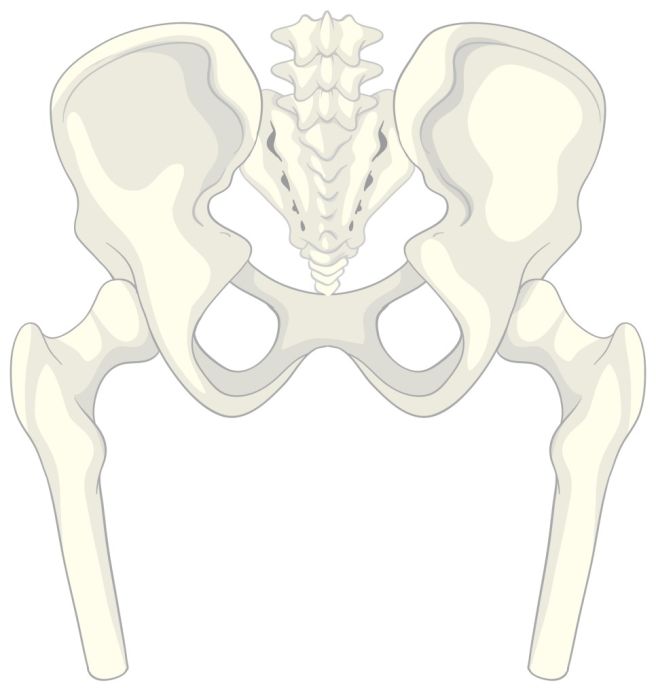

대퇴부 위치와 기능

대퇴부는 인체의 골격 구조 중에서 허벅지에 해당하는 부위로 고관절부터 무릎관절까지 이어지는 구간을 말합니다. 대퇴부에는 신체에서 가장 크고 길며 강한 뼈인 대퇴골이 중심을 이루고 있습니다.

대퇴골은 체중을 지탱하는 역할을 하며, 직립 보행을 가능하게 하는 데 필수적인 구조입니다. 상단은 골반과 연결되어 고관절을 이루고 있으며, 하단은 경골과 만나 무릎관절을 형성합니다. 이 뼈는 단순한 지지 구조물에 그치지 않고, 보행 시 충격을 흡수하고 전달하는 기능도 수행합니다.

대퇴부는 단순히 뼈로만 이루어진 것이 아니라, 대퇴사두근, 햄스트링 등 여러 근육과 인대, 신경, 혈관이 함께 구성되어 있으며, 움직임의 방향과 강도를 조절하고, 주변 조직에 산소와 영양분을 공급하는 데 관여합니다.

대퇴부는 신체 활동의 중심이 되는 부위로 균형 유지, 자세 조정, 계단 오르기, 앉고 일어서기 같은 동작을 가능하게 합니다. 따라서 대퇴부에 이상이 생기면 이동 능력과 신체 기능 전반에 영향을 미칠 수 있습니다.